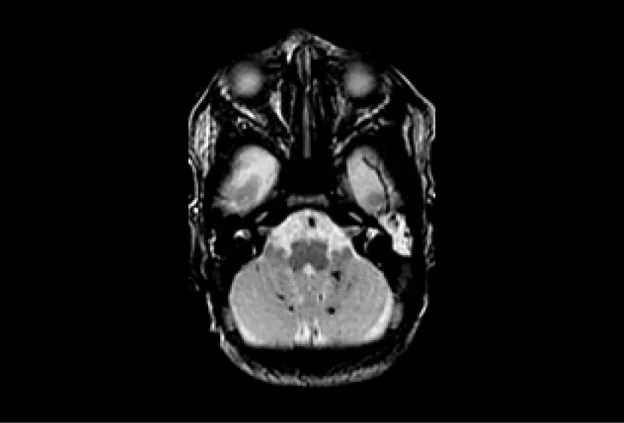

Fetal MRI Study

The Fetal MRI study is developing methods to better assess and quantify development of the nervous system in the fetus, thereby allowing early detection of developmental abnormalities. In addition, the study is comparing how accurately fetal MRI detects changes in the fetus’ brain and spine during pregnancy compared to ultrasound.

MRI image of a 30 week fetus shows normal fetal brain on this sagittal image (acquired in the midline of the brain). Notice how much detail can be seen of the foldings (sulci and gyro) of the brain, the brain stem, and the cerebellum.

UCSF is one of the few sites in the country that is experienced with performing and interpreting fetal MRI. We have performed fetal MRI since 1996. The findings from our fetal MRI study will help us provide pregnant women with the most advanced and accurate information during their pregnancy.

First, we would like to see how accurately fetal MRI detects changes in the fetus’ brain and spine during pregnancy compared to ultrasound.  While ultrasound is the most commonly used method of monitoring fetal development, its ability to detect changes in the brain is limited.  In this study, we are comparing ultrasound and MR images of fetuses to identify the situations in which fetal MRI will provide valuable clinical information not seen on ultrasound.  Studies have shown that, overall, fetal MRI is more helpful than ultrasound in evaluating the brain. We are interested in studying just how helpful fetal MRI is for different brain conditions.

Second, we would like to learn how various congenital (inherited) and acquired abnormalities detected on fetal MRI correlate with childhood development.  Currently, it is very difficult to counsel parents who have a fetus with a brain abnormality, because outcomes can vary widely.  By classifying abnormalities more thoroughly with fetal MRI, we will be able to give parents a more accurate picture of what they can expect for their child from a neurological and developmental standpoint. This information will help parents make decisions during pregnancy and prepare in advance for challenges their child and family may face.